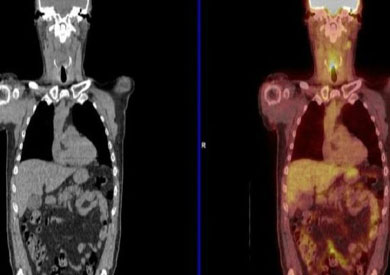

الصورة الملونة تظهر النقاط السرطانية، وإحداها في الحلق

وتستخدم تقنية تصوير مقطعي بالإصدار البوزيتروني (PET-CT) صبغة ذات إشعاع نشط خلال المسح المقطعي، والتي تحدد الخلايا السرطانية التي تنقسم بسرعة.

وذلك يسمح للأطباء برؤية ما إذا كانت هناك خلايا سرطانية مازالت حية في الرأس أو الرقبة.

وقال البروفيسور هشام مهنى، من جامعة برمنجهام، لبي بي سي نيوز: "إن الخلايا السرطانية تختفي بين الخلايا الميتة، وباستخدام PET-CT يمكن معرفة ما إذا كانت مازالت حية أم لا."